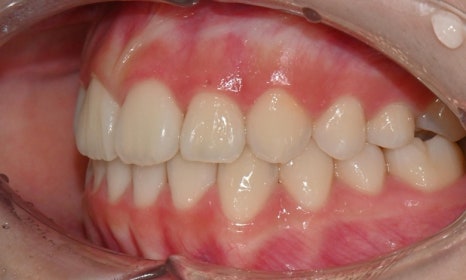

2025.3. 초진 (앞니 경미한 총생과 과개교합) - 연세정원치과

정밀진단 결과 위아래 앞니가 약간 겹쳐 있어 배열이 고르지 않은 상태였으며, 약간의 과개교합이 동반된 상태였습니다. 다만 골격적인 문제나 안모 불균형은 없었고, 측면에서도 돌출감 없이 비교적 안정적인 안모를 유지하고 있었습니다.

이러한 점을 종합적으로 고려해보았을 때 치아 배열의 개선과 교합 조정을 중심으로 한 비발치 교정 치료가 적합한 케이스였습니다. 또한 환자가 고등학생이라는 점, 그리고 학업과 일상 생활에 대한 부담을 최소화하고 싶다는 보호자의 의견을 반영하여, 인비절라인으로 선택하게 되었습니다.